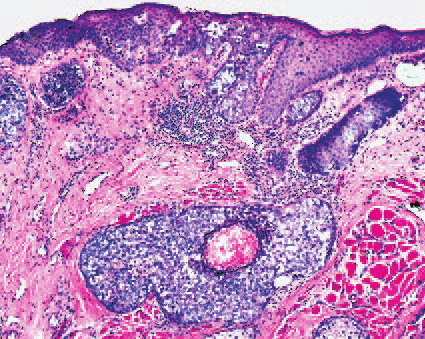

Sebaceous carcinoma = الكارسينوما الدهنية